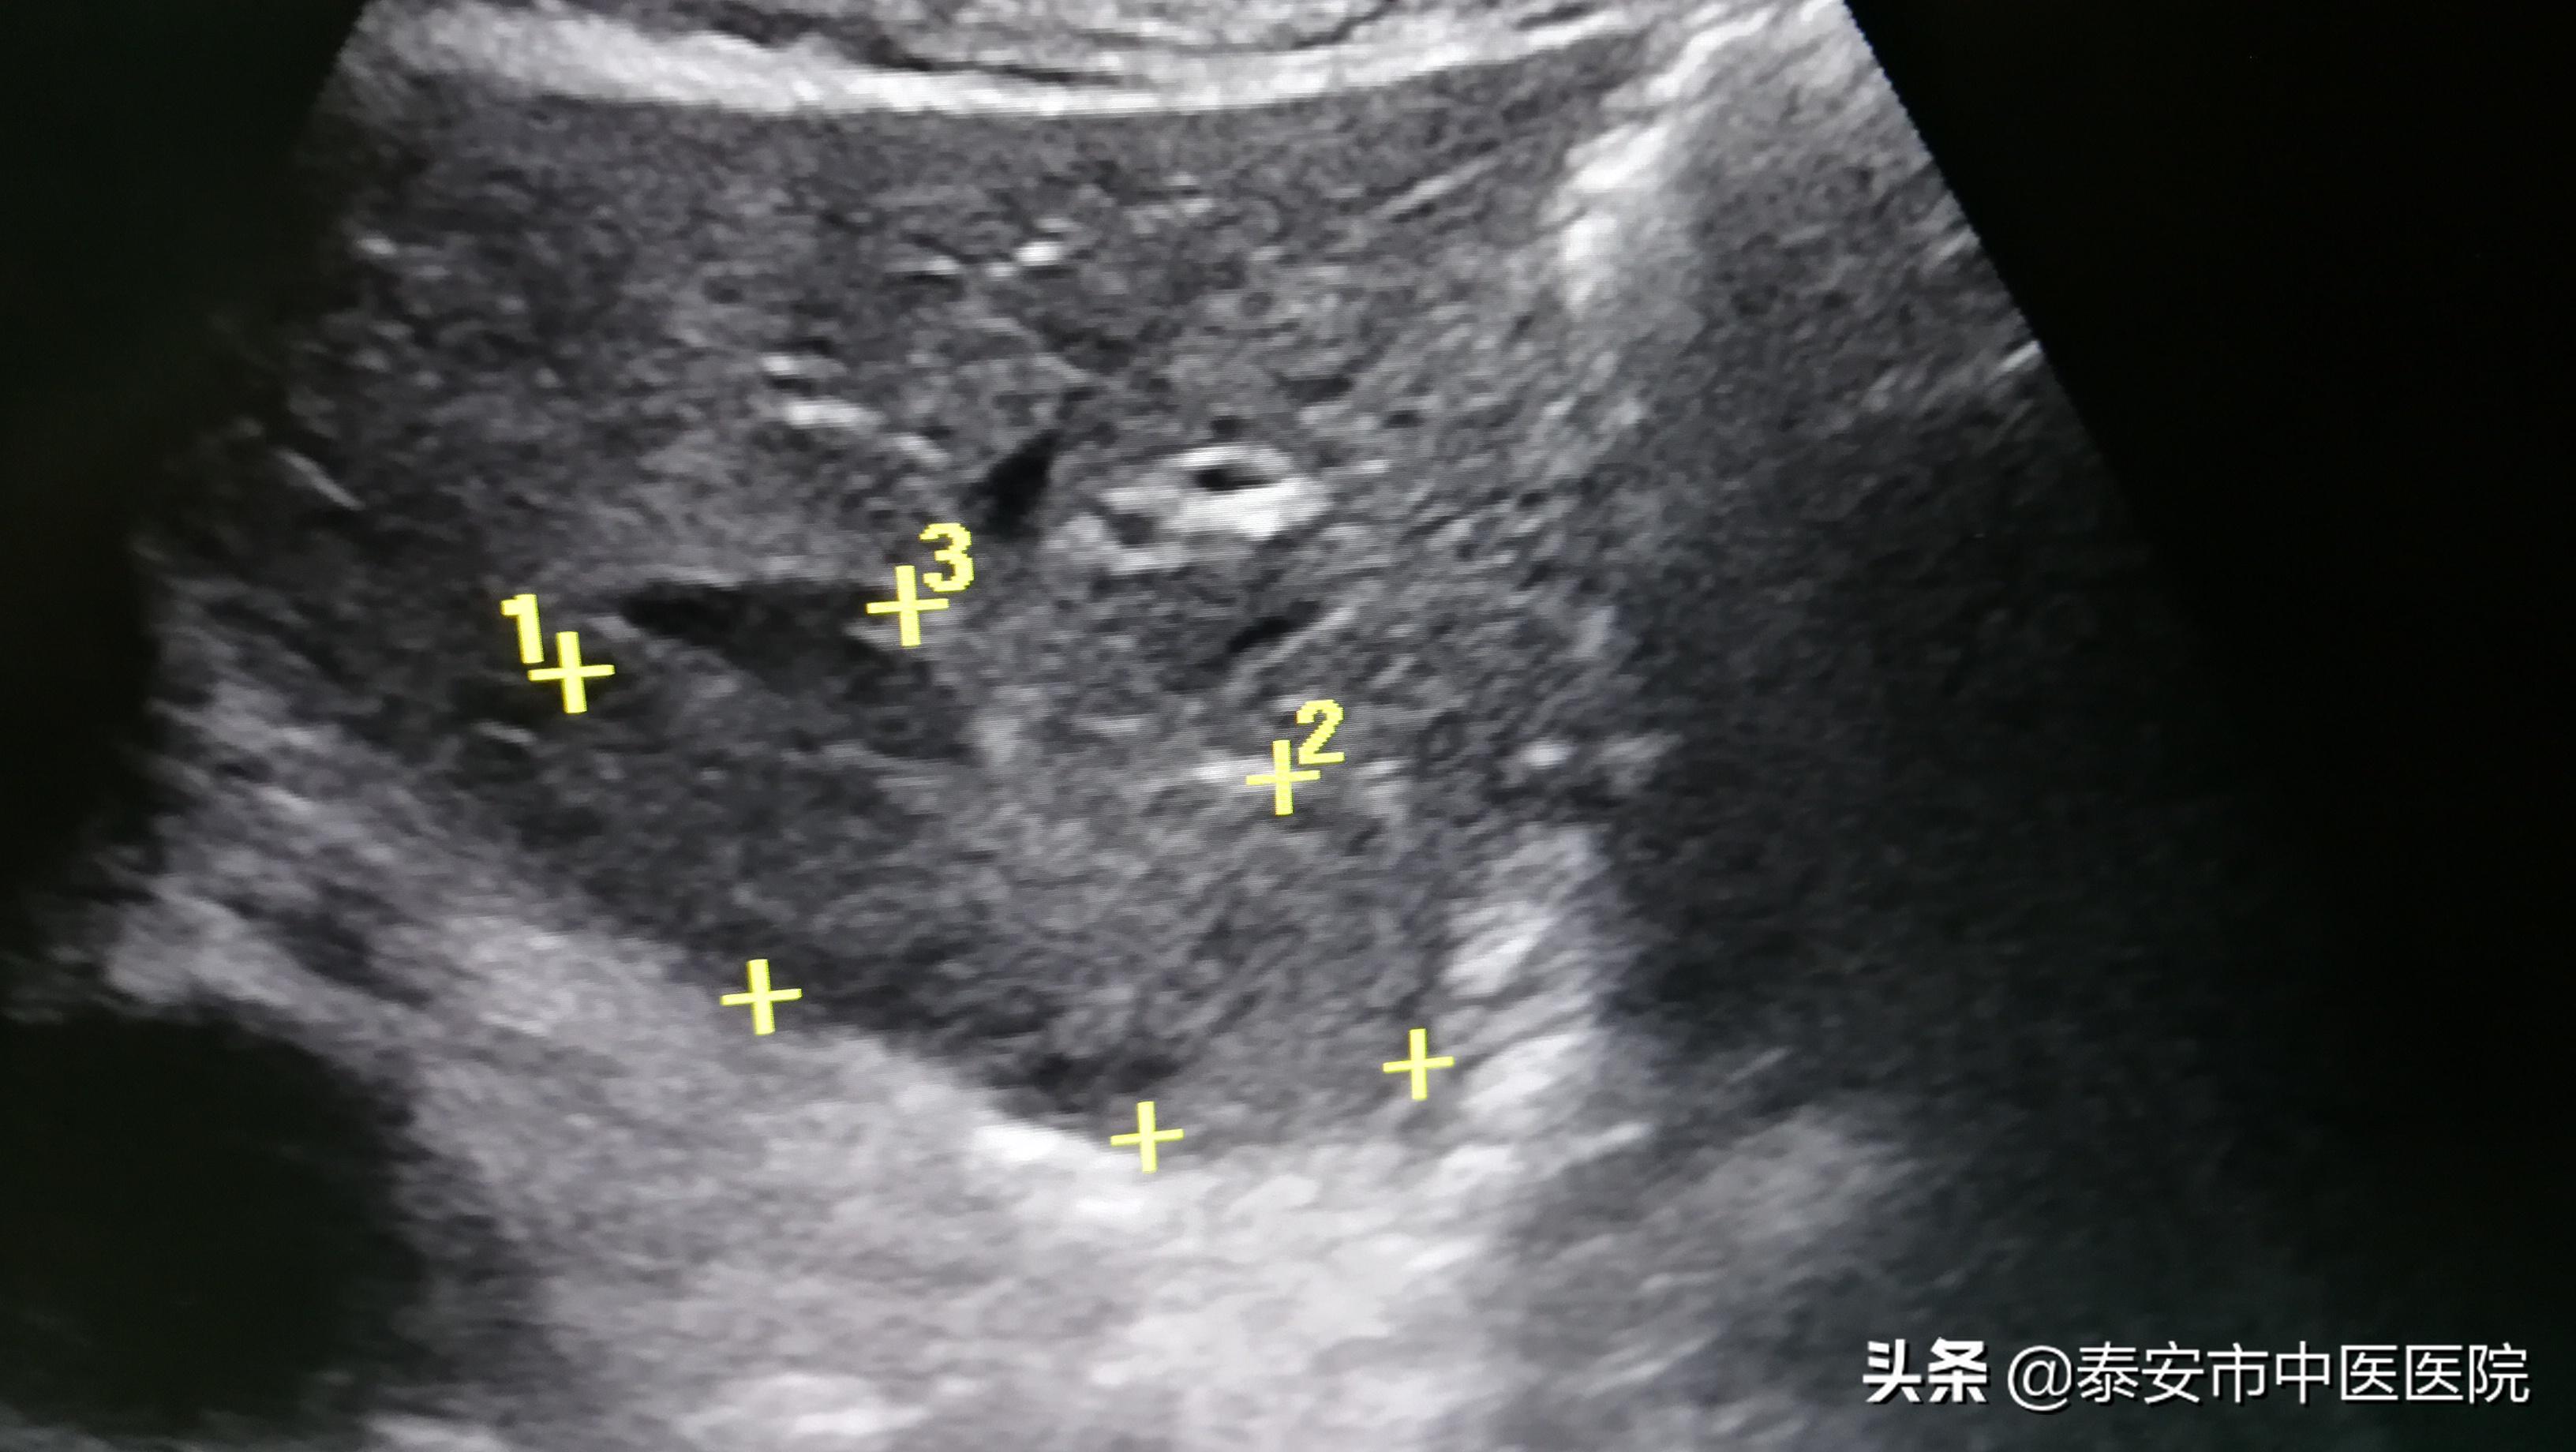

血管瘤消融后

超声介入科特聘专家梁波教授会诊后,经与患者及家属充分沟通并同意后,决定在我院超声介入科行肝血管瘤超声引导下经皮穿刺微波消融术。术中,梁波教授基于深厚的超声功底和精准的穿刺技术,将微波消融针精准穿刺进入肿瘤内,施加微波加热治疗,10余分钟手术成功完成,术后伤口不足2mm。